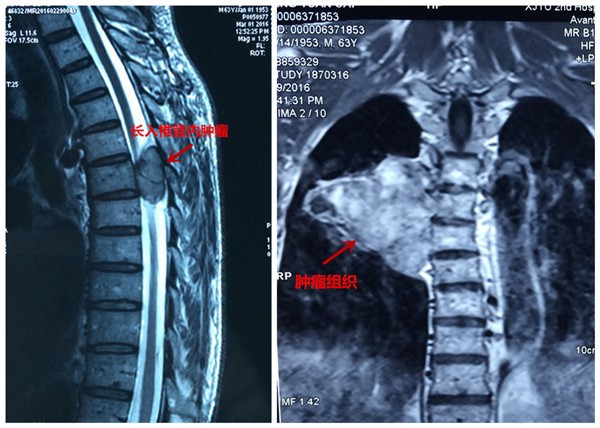

患者彭某,男,63岁,以胸背部疼痛5年,双下肢无力麻木半年之主诉入院,5年前无明显原因出现胸背部疼痛,影响夜休,就诊于当地医院,给与对症治疗,效果欠佳,背痛逐渐加重,长期服用非甾体类止痛药止痛,半年前无明显原因出现双下肢麻木、无力,走路不稳,进行性加重,未做治疗,2016年3月初就诊于当地医院,行胸椎MRI:胸6椎体水平椎管内外实质性暂未并胸6椎体附件、右侧第6肋骨骨质破坏,考虑恶性肿瘤可能,全身骨显像提示胸6椎体及右侧第6肋骨代谢异常活跃,恶性病变可能性大。当地医院拒绝治疗,为求进一步诊治,来我院门诊以“脊柱肿瘤”之诊断收入院。发病来食纳差,睡眠可,大小便正常,体重无明显变化。专科情况:脊柱生理弧度可,胸6棘突及附件压痛叩击痛阳性,半双下肢抽痛,双下肢肌张力可,肌力约3级,平乳头以下肢体感觉减退,无汗,双侧膝腱反射及跟腱反射阴性,双侧巴氏征阴性,左侧踝阵挛阳性。

患者入院后,王栋副主任,李锋涛主治医师高度重视,仔细询问患者病情,进行专科查体,分析以往患者的影像学资料,由于肿瘤组织生长巨大,严重压迫右肺,并且已经破坏了胸6椎体及其附件、右侧第6肋骨等,局部结构复杂,为了帮助手术方案的设计,我们采用3D打印技术,术前将肿瘤局部解剖结构打印成3D模型。邀请胸外科张维教授多次会诊,根据3D打印模型制定了详细的手术计划及围手术期治疗方案。经过严密的手术前准备,以王栋副主任、张维教授为主刀、李锋涛主治医师为助手,吴刚副主任医师、罗斌医师为麻醉医师,殷敏、马霞为配合护士,黄亚娟、王芳医师为术中诱发电位监护医师的手术团队努力下,手术顺利完成,成功切除了胸腔内、椎体旁及椎管内肿瘤组织,并进行了脊柱的重建。术后患者恢复良好,很快下肢感觉、肌力恢复,现患者正在康复中。